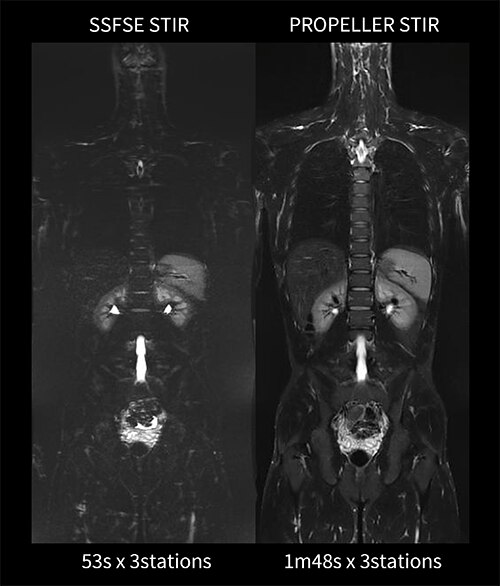

Case2 乳腺外科:乳癌の全身検索目的

40代、女性。乳癌術後にて5年前に肝転移に対して治療開始。その後、CTにて骨転移とリンパ節転移を認め、全身検索目的にてWBDWIを施行した。WBDWI(①)とFusion(②)で上腕骨、肋骨、椎体、大腿骨など多発骨転移が認められる。CT(③)では椎体の中心に石灰化(➞)を認めるが、DWI(④)とFusion(⑤)では無信号であることから良性石灰化を疑う所見である。CT(③)の石灰化周囲(➞)にDWI(⑦)で高信号を認め、溶骨性骨転移を示唆する所見である。また、仙骨にも同様のCT(⑥)の低吸収域(➞)にDWI(⑦)でも同部位に高信号を認め、溶骨性骨転移が疑われる(図11)。依頼医からは、乳癌のフォローは長期にわたり定期的に画像検査を行う必要があるため、WBDWIは被ばくがなく、繰り返し検査を行うことが可能であるため非常に有用であると評価が得られた。

図11 乳癌術後の全身検索目的